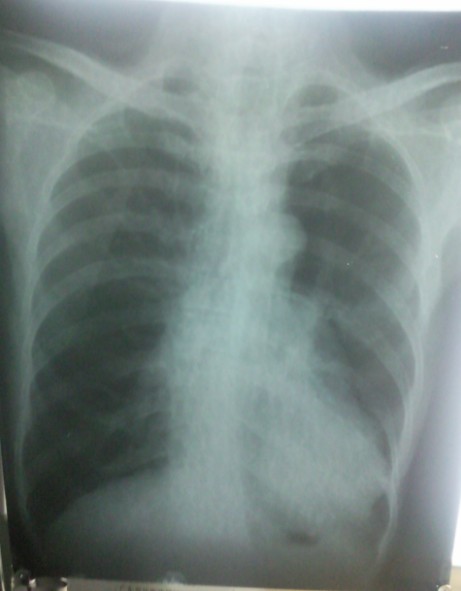

患者男,50岁,反复咳嗽、咳痰10余年,加重并气促3天。

片子质量不好,肺气肿肺心病

慢支肺气肿,肺心可能。

慢支,肺气肿,肺心病可能。

慢性支气管炎、肺气肿、肺心病。

建议心脏彩超。

建议加照侧位,或ct检查除外左下肺或纵膈病变。

考虑慢支、肺气肿、肺心病,请结合临床。

慢支、肺气肿。是否肺心病可以做个心电图看看

慢支、肺气肿,左下肺感染,肺心?

慢性支气管炎,肺气肿;肺原性心脏病。